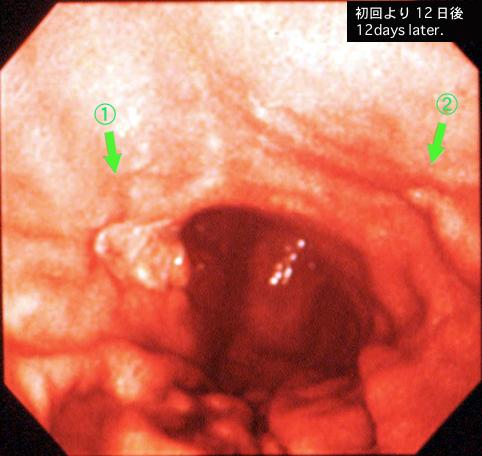

疾病(病理主体)的分类恶性淋巴系统肿瘤/MLP型恶性淋巴瘤

部位(按器官分)胃(部位)/2个以上

检查方法内窥镜

肿瘤最大直径20~24

多发性肿瘤(同一器官)有(同时性)